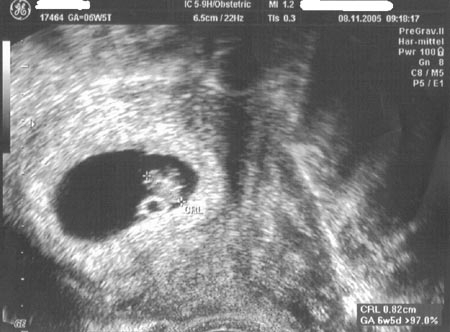

На этом сроке с помощью УЗИ-аппарата уже можно услышать биение маленького сердечка. Начиная с шестой недели беременности, частота сердечных сокращений будет увеличиваться и к концу седьмой недели достигнет 110 ударов в минуту.

Вес и размер плода на 7 неделе беременности

Установить размеры плода и примерно оценить его массу возможно с помощью ультразвукового исследования. На данном этапе беременности размер плода измеряется по копчико-теменному размеру (КТР), который в среднем составляет от 8 до 13 мм, а длина плода достигает 19 мм. На седьмой неделе беременности средний вес плода составляет около 1 грамма. Вы можете ознакомиться с фотографиями УЗИ по неделям беременности, которые помогут вам лучше понять, как развивается ваш малыш в утробе.

УЗИ на 7 неделе беременности

На седьмой неделе беременности с помощью ультразвукового исследования можно оценить развитие эмбриона и его сердечный ритм, который составляет от 110 до 130 ударов в минуту. На изображении отчетливо виден желточный мешок, который выглядит как светлый контур, а его внутреннее содержимое отображается в виде темного пятна.

На ультразвуковом исследовании также можно легко определить наличие двойни.